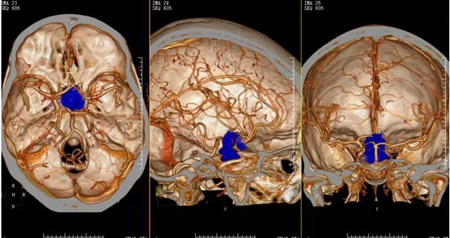

▲图2:2018-01-10术前CTA示双侧颈内动脉虹吸部受压、外移,邻近willis环稍扩大